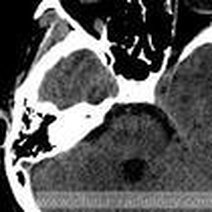

- 数字减影血管造影技术,颅内动脉瘤介入治疗,湘雅护理学院,颅内动脉瘤,颅内动脉瘤系指脑动脉壁的异常膨出部分,是引起自发性蛛网膜下腔出血的最常见原因。病因-尚不甚清楚,但以先天性动脉瘤占大部分。任何年龄可

- 动瘤DavidSLiebeskind1引1.1景动瘤是有破倾向的管结构的病理性局灶性扩张。些管异常常根据假定的病因分类。囊状、浆果状或先天性动瘤占全动瘤的90

- 脑动脉瘤相关知识脑动脉瘤简单说就是脑动脉血管壁上膨出的血管泡,血管泡在血液不间断的冲击下,就象吹气球一样,球吹得越大,血管壁就变得越薄,血管也就越容易破裂。一般认为